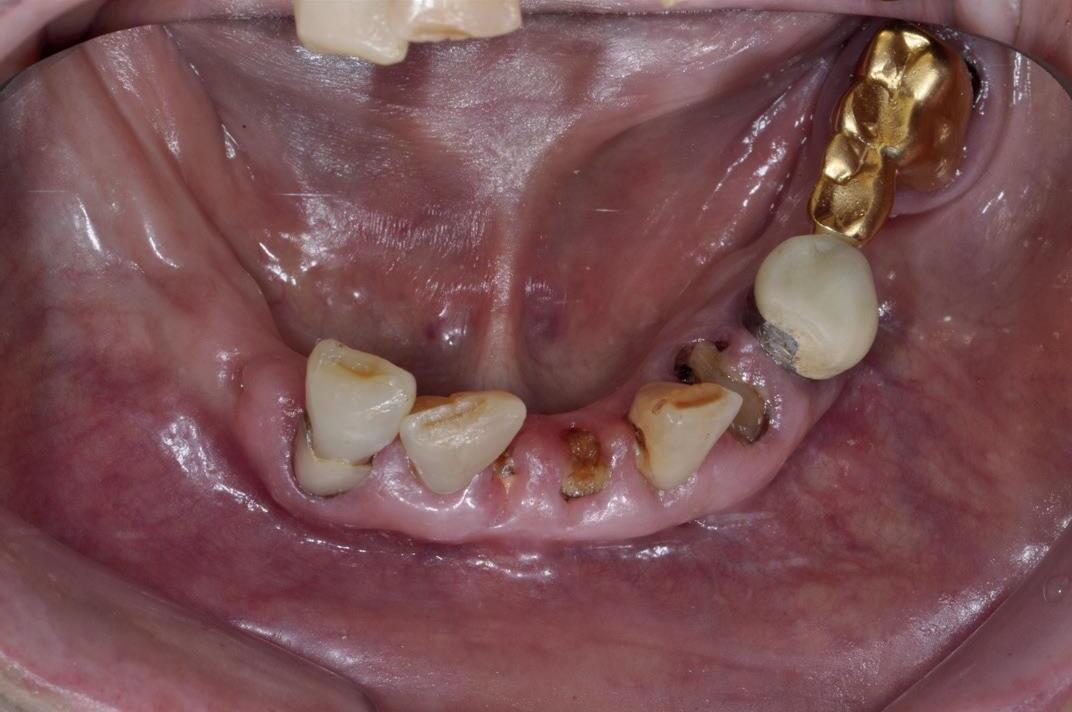

1. “rampant caries” is een groot probleem bij patiënten met een droge mond. Indien niet tijdig wordt ingegrepen gaan de tanden en kiezen vroegtijdig verloren.

Gevolgen van een droge mond

Speeksel speelt een cruciale rol in het handhaven van een gezonde mondholte. Het merendeel van de patienten met een tekort aan speeksel ondervindt chronische monddroogte, waardoor processen als eten, slikken en praten niet meer vanzelf verlopen. Verder ervaren patiënten vaak klachten als pijn in de mond, een droge keel, smaakverlies en slapeloosheid. Bovendien gaat het wegvallen van speeksel ten koste van de natuurlijke afweer in de mond, waardoor het risico van verschillende aandoeningen aanzienlijk toeneemt, zoals schimmelinfecties. Candida albicans profiteert van een droge mond, wat leidt tot candidiasis.

Vooral het ontstaan van een snel voortschrijdend cariësproces is een opvallend probleem. Door de afgenomen speekselvloed en de veranderde speekselsamenstelling treedt er een microbiologische ‘shift’ op. Daarnaast zal de bescherming tegen cariogene bacteriën afnemen door veranderingen in de pH, buffercapaciteit en functioneren van bepaalde eiwitten. Verder neemt de natuurlijke reiniging van de mond door de speekselvloed (oral clearance) af. Behalve voor cariës zijn patiënten met een speekselklierdisfunctie ook bovengemiddeld vatbaar voor tanderosie. Tanderosie wordt voornamelijk aangetroffen bij patiënten met een droge mond die hun speekselsecretie

2. een tong met veel en diepe fissuren wordt vaak gezien bij patienten met een droge mond

stimuleren met zuurprikkels. Indien patiënten zure dranken gaan gebruiken om het gevoel van een droge mond tegen te gaan, hebben zij een grote kans op het ontstaan van tanderosie.